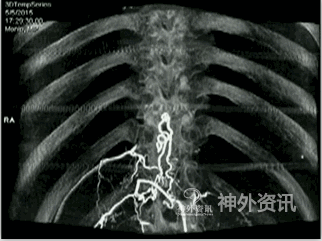

脊髓血管造影,尤其是经皮穿刺股动脉选择性脊髓血管造影,是诊断脊髓血管疾病的金标准。至今,由于影像技术、DSA血管造影机诸多后处理功能的进步,如三维成像技术(three-dimensional imaging technology;图1)、最大密度投影成像(maximum intensity projection,MIP;图2)、双容积重建(double volume,DV;图3)与三维影像融合技术(three dimensional image fusion technology;图4)及我们研究开发的三种技术的动态成像技术(dynamic image fusion technology),可以给出冠状位从前到后再从后到前、矢状位从左到右再从右到左、轴位从上到下再从下到上的全方位多角度动态立体解剖影像(图5),就更提高了对脊髓血管疾病诊断的认识和治疗水平。因此,应该说这些三维融合影像才是脊髓血管疾病诊断的金标准[1,2]。

②选择性肾静脉造影,注入非离子造影剂(7ml/s、总剂量10ml),使肾静脉显影,了解肾静脉有无狭窄、闭塞,或向下腔静脉回流障碍而经肾椎静脉干返流向椎管内静脉,引起椎管内静脉高压综合征[8],导致脊髓功能受损。对动脉造影阴性,而又不能排除脊髓静脉高压综合征者,应做选择性左肾动脉造影,了解左肾静脉向下腔静脉回流有无障碍(图13)。

③经股静脉穿刺插管进入上腔静脉、下腔静脉,分别将造影导管超选择逆行插入奇静脉、半奇静脉、副奇静脉与腰1~4橫静脉[9],注入非离子造影剂(5ml/s、总剂量7ml),了解这些静脉有无向下腔静脉回流障碍,导致脊髓静脉高压综合征。如这些静脉有狭窄、闭塞,或造影剂不能向上、下腔静脉回流时,就返流经椎管内静脉回流至脊髓表面正常引流静脉,引起脊髓静脉高压综合征,导致脊髓功能受损(图14)。

图13: 左肾静脉狭窄致脊髓静脉高压综合征,红色↑示肾静脉狭窄,绿色↑示向肾椎静脉回流。

图14: 第三腰横静脉狭窄致脊髓静脉高压综合征A~C. MRI,红色↑示血管流空影;D、E. 第三腰横静脉造影,红色↑示左第三腰横静脉狭窄,绿色↑示向下腔静脉回流少,蓝色↑示向脊髓静脉回流;F. 球囊扩张治疗第三腰横静脉狭窄致脊髓静脉高压综合征,黄色↑示扩张球囊;G. 球囊扩张后,黑色↑示狭窄腰横静脉向下腔静脉回流通畅。